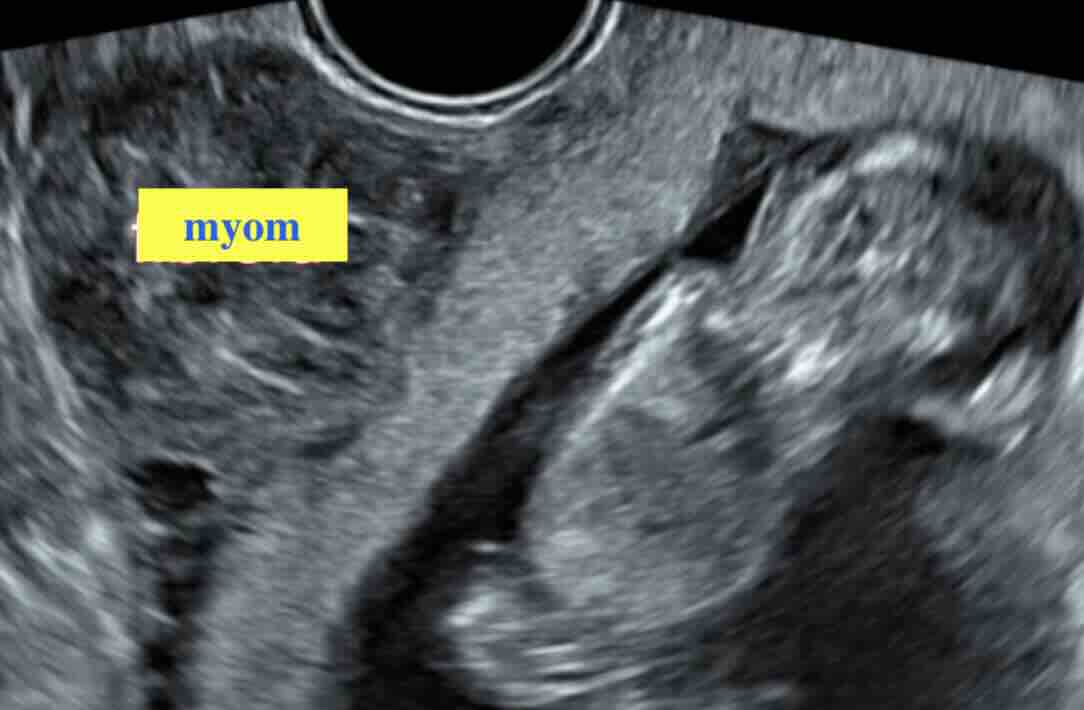

Polip veya miyom şüphesi

Polip/miyom varsa HSG’de çıkar mı?

HSG rahim içi boşluğun şeklini gösterir ve polip/miyom şüphesi oluşturabilir. Ancak kesin tanı için çoğu zaman ultrason, SIS (salin sonohisterografi) veya histeroskopi daha net bilgi verir. -